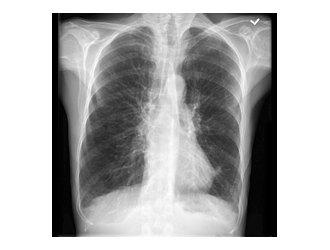

- A chest X-ray